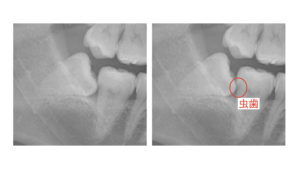

②手前の歯が虫歯になる

斜めになった親知らずと手前の歯との間は歯磨きをすることが難しく、虫歯になってしまうことがよくあります。

虫歯になった場合、親知らずを抜歯してから虫歯の治療をすることとなります。

この場合虫歯を削り取り詰め物をすることで治療完了です。

ただしこの部分の虫歯治療は非常に大変で予後もあまり良くありません。

また、治療手段もかなり限られてきます。

大きな虫歯にってしまった場合は歯の中の神経まで取り除く必要が生じてしまいます。

親知らずがなければ手前の歯の神経は残せたかもしれないので、この状態になるまでに抜歯をするべきでしょう。